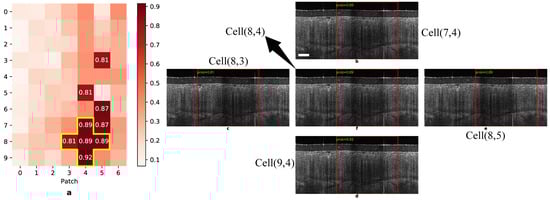

2.3.5. OCT Volume Label Prediction

Because the DL model only outputs the label of a given cervical OCT image, we need to predict an entire volume’s category by aggregating the prediction results of all patches it contains. Despite the existence of the majority voting rule and machine learning-based approaches, we used a cross-shaped threshold voting rule [21] to interpret patch-level predictions. That is to say, a cervical lesion in a 3D OCT volume can be detected in consecutive high-risk patches defined by a threshold from the cross-sectional (in-frame) and axial (cross-frame) directions. Such a pattern looks like a cross, which is straightforward and explainable for gynecologists. Figure A2 illustrates an OCT volume of HSIL identified using the cross-shaped threshold voting rule. As with colposcopy-directed biopsy, a subject is positive (or high risk) if one of her cervical OCT volumes is diagnosed as positive.

Appendix A.2. Cross-Shaped Threshold Voting

The authors of a previous work [21] developed a cross-shaped threshold voting strategy to aggregate patch-level predictions into a single label for the entire OCT volume. Its main goal is to find a series of high-risk patches resembling a cross shape in both axial and cross-sectional directions. Figure A2 illustrates the cross-shaped threshold voting strategy. In this cervical OCT volume, the method detected five high-risk patches (probability > 0.8), including the fifth patch in the eighth, ninth, and tenth frames and the fourth, fifth, and sixth patches in the ninth frame. Together, they constituted a cross. As a result, the predicted label of this volume was positive.

Figure A2. An illustration of the cross-shaped threshold voting strategy [21]. Scale bar: 200 μm.

Diagnostics 14 02009 g0a2